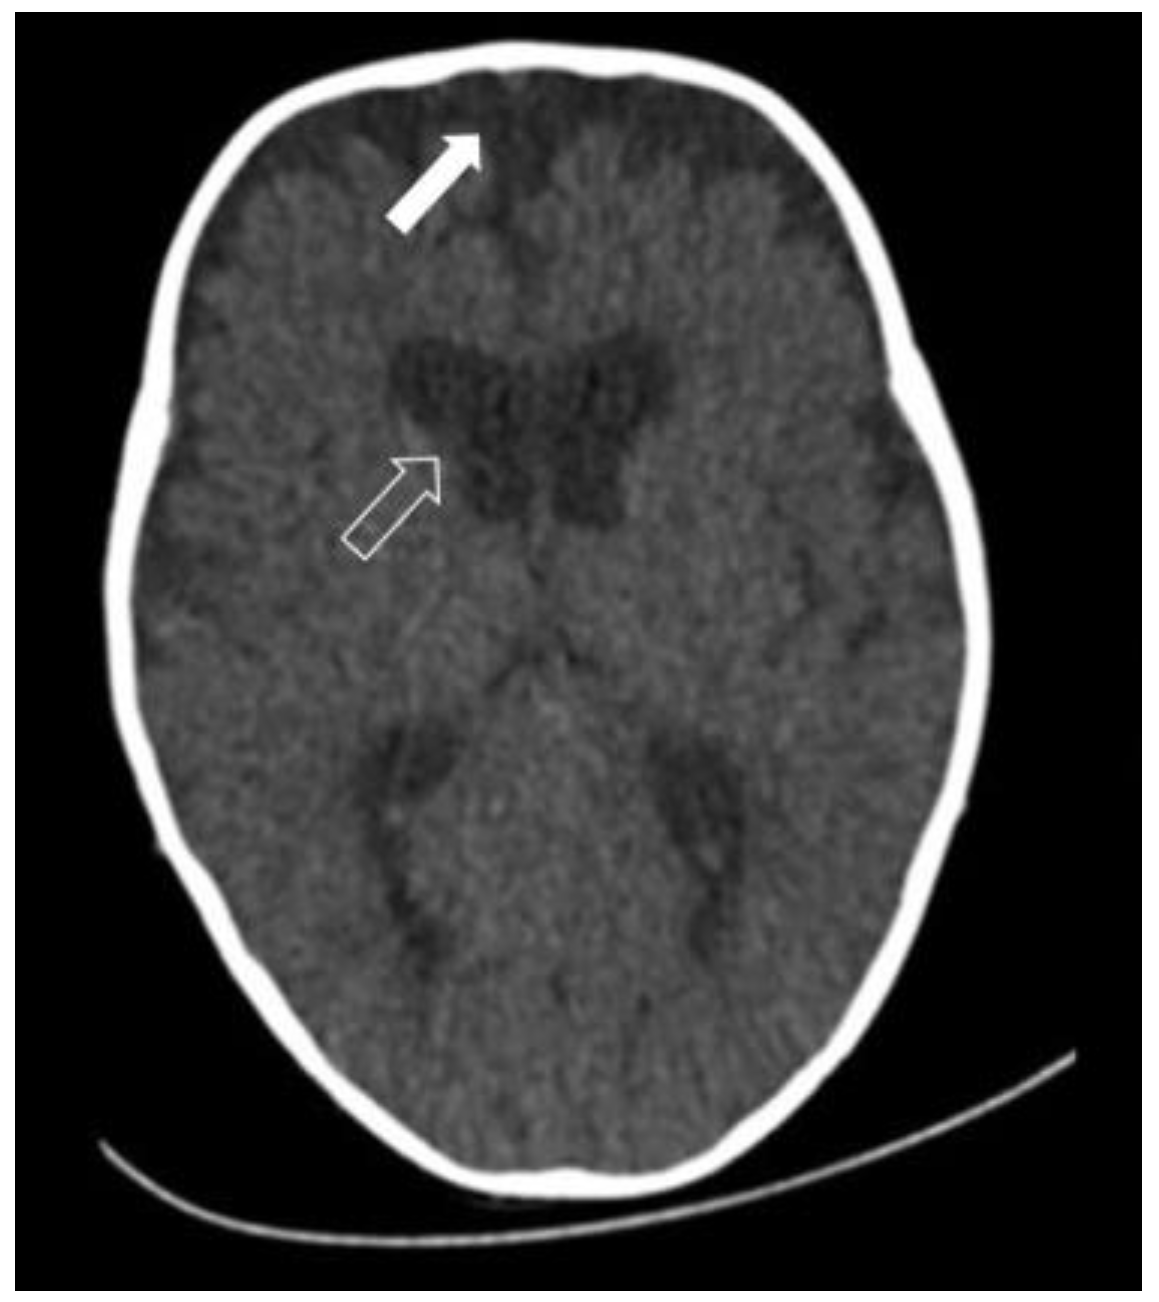

3. Radiology

- the above-mentioned passive accumulation of CSF in the subarachnoid spaces as a result of morphological enlargement in the frontal region; and

- CSF retention as a result of a disturbance in the process of CSF resorption [14].

- Usami, K.; Nicolini, F.; Arnaud, E.; Di Rocco, F. Cerebrospinal fluid collections in sagittal suture synostosis. Childs Nerv. Syst. 2016, 32, 519–525. [Google Scholar] [CrossRef]